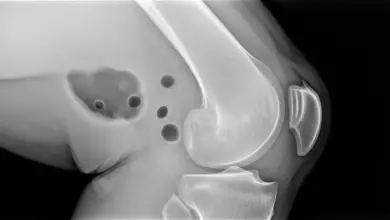

A fissura condral é uma falha na cartilagem do joelho. Em alguns casos, ela atinge uma camada mais superficial.

Em outros, o dano avança para áreas mais profundas e pode se associar à alteração do osso logo abaixo da cartilagem.

Esse tipo de lesão pode surgir por trauma, torção, sobrecarga repetitiva, desgaste progressivo ou alteração biomecânica da articulação.

Também pode aparecer junto de lesões meniscais, instabilidade ligamentar e desalinhamentos que aumentam a pressão em pontos específicos do joelho.

Na prática, a ressonância magnética é o exame que melhor mostra a extensão da lesão, porque permite avaliar a cartilagem, o osso abaixo da superfície articular, os meniscos e os ligamentos com mais detalhe.

Quando existe dúvida diagnóstica ou indicação de tratamento cirúrgico, a artroscopia pode ser utilizada para visualizar a área lesionada de forma direta.